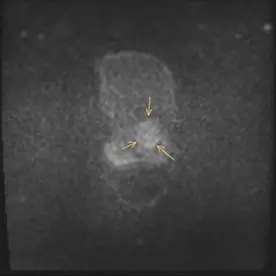

Es erfolgte eine multiparametrische MRT der Prostata mit intravenöser Kontrastmittelgabe. Neben einer Prostatahyperplasie mit ca. 47 ml Volumen zeigte sich der Nachweis von 2 malignitätssuspekten Läsionen.

Die Läsion 1 liegt in der Transitionszone links paramedian basal und im mittleren Drüsendrittel mit einer Signalminderung in T2w (Bild 1), Diffusionsstörung (Bild 2) und Korrelat in der DCE. Die Größe der Läsion beträgt ca. 25x20x28mm, sie zeigt keine Überschreitung der Kapsel und keine Invasion in das neurovaskuläre Bündel (Bild 5). Die Läsion wurde als PI-RADS 5 klassifiziert und hat somit ein sehr hohes Malignitätsrisiko.